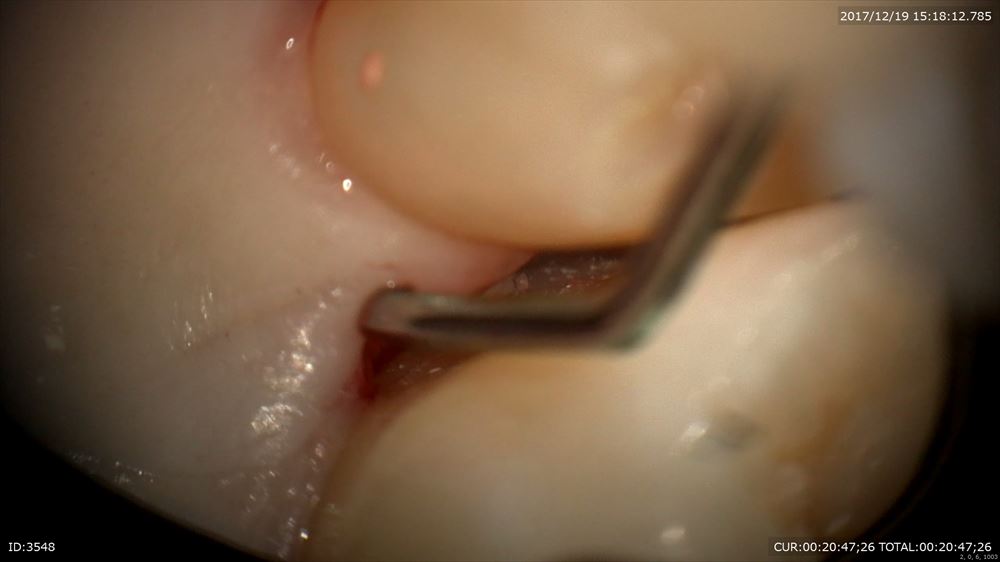

もう1つのケースはインプラントと再生療法を同時に行った方の被せ物セットもマイクロスコープ治療で

歯周病だったと思えないくらい歯肉は綺麗。患者さまのプラークコントロールに助けられています。

セット。お正月が楽しみ!お餅。数の子!!